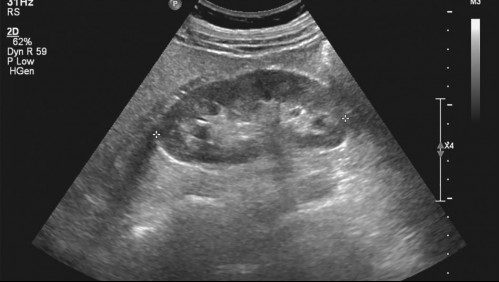

Mundo Fue a realizarse una ecografía para después operarse y los doctores descubrieron que tenía 3 riñones